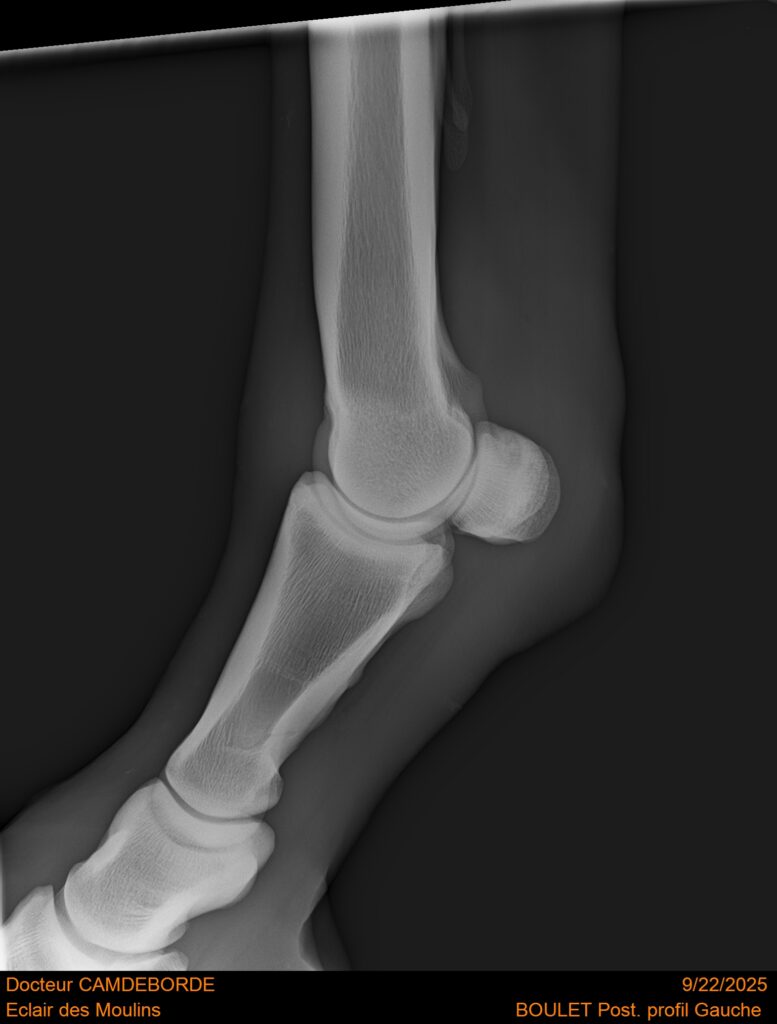

10 K ✨ TOP cheval pour épreuve Amateur ! ECLAIR DES MOULINS, selle Français de 11 ans. Classé sur 1m05. Idéal pour aller faire jusqu’à 110 voir 115, cheval pas usé (une vingtaines de parcours). Très gentil au quotidien, cheval de famille. Courageux et respectueux à l’obstacle. Bien dressé, change de pieds. Bilan pieds, boulets, jarrets, grassets et visite clinique effectuée cette semaine. il peut vivre au box comme au champs, cheval rustique. toise environ 1m60 porteur. Pour le compte de son propriétaire car manque de temps.

RADIOS ET CLINIQUE